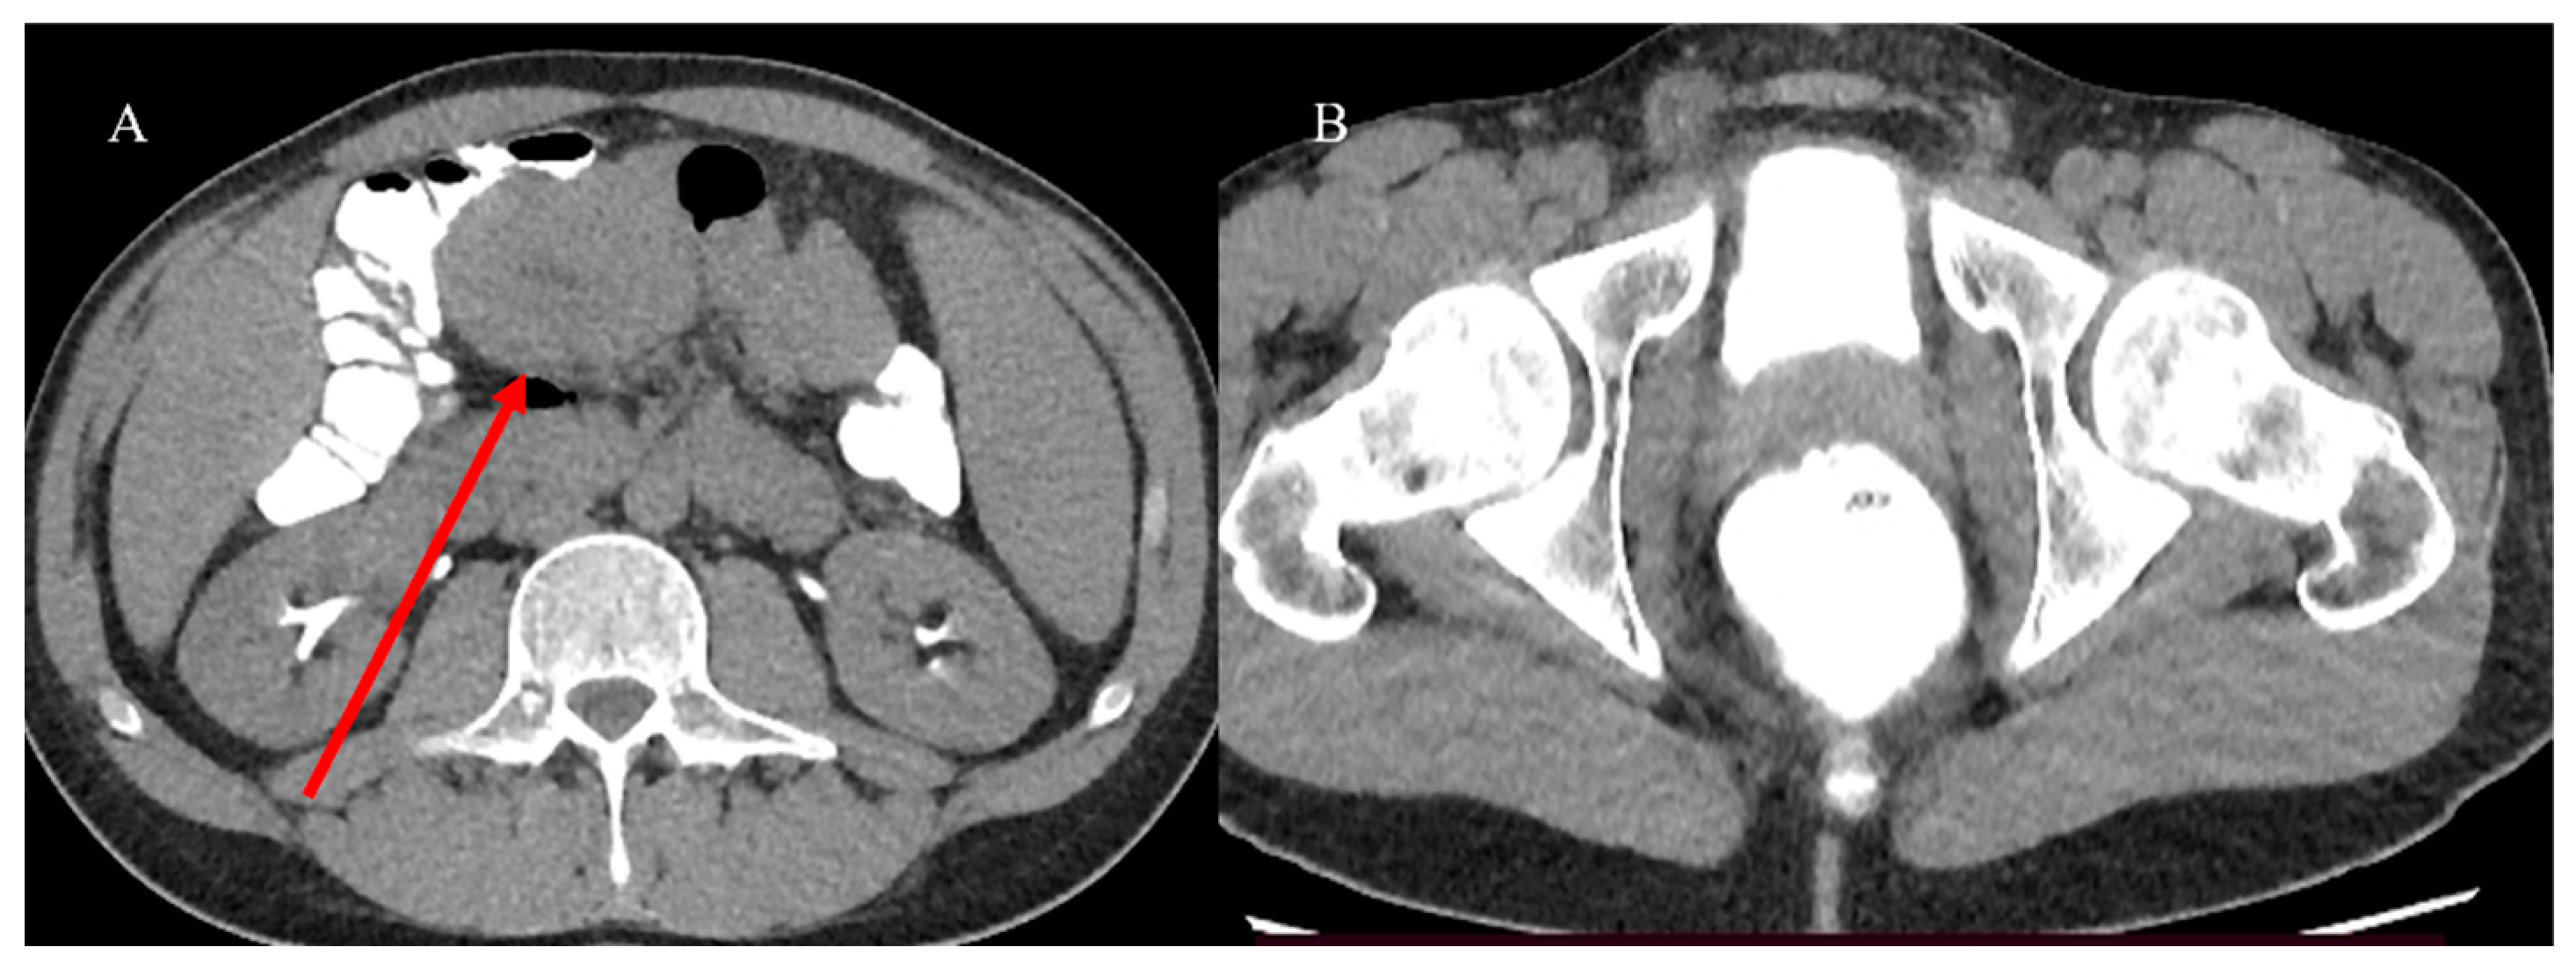

- Nelms, D.W.; Kann, B.R. Imaging modalities for evaluation of intestinal obstruction. Clin. Colon. Rectal Surg. 2021, 34, 205–218. [Google Scholar] [CrossRef]

- Paulson, E.K.; Thompson, W.M. Review of small-bowel obstruction: The diagnosis and when to worry. Radiology 2015, 275, 332–342. [Google Scholar] [CrossRef] [PubMed]

| CECT | In an emergency and initial staging of SBTs | A good arterial phase (30–35 s) for higher-vascular SBT tumors as NETs and GI bleeding | Speed; easier availability; MPR reconstruction | Small intestinal tumors may be not visualized without distension; allergy to contrast agents |